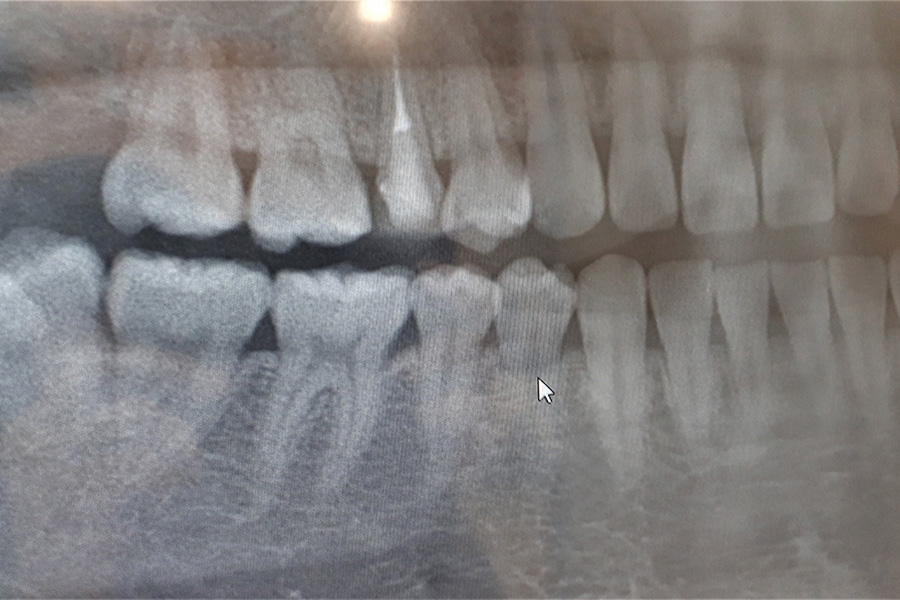

当院では必要に応じて歯科用レントゲンを活用し、歯の根や親知らずの状態を把握したうえで、正確な診断と処置を行っています。当院での処置が難しい手術が必要となる場合には、適切な医療機関をご紹介させていただきます。

親知らずとは、10代後半から20代にかけて生えてくる奥歯のことです。

あごのスペースが足りず、斜めや横向きに生えるケースも多く、周囲の歯に悪影響を及ぼすことがあります。違和感や痛みがある場合は、早めに受診して状態を確認しましょう。